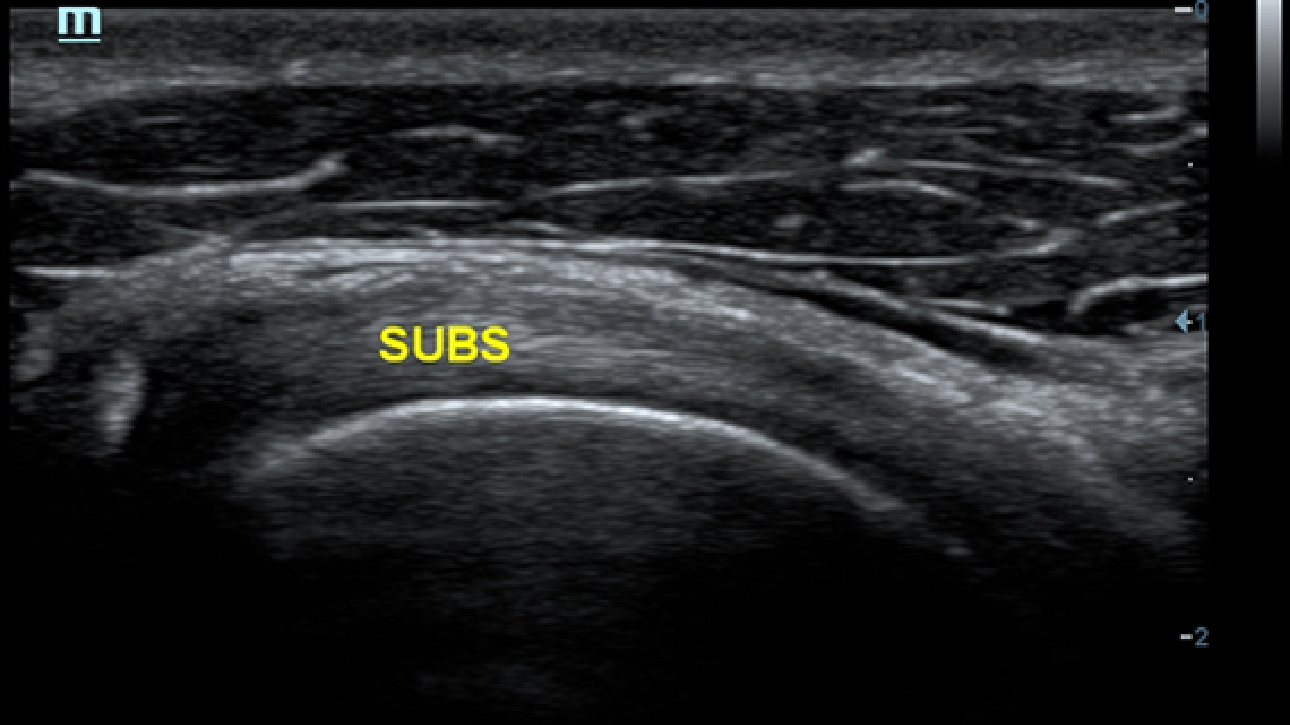

Obrazy kliniczne